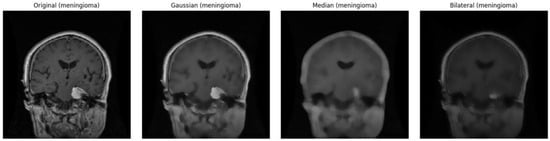

- In the data preprocessing, images in the dataset have been balanced and augmented using Wasserstein Generative Adversarial Network (WGAN) to generate synthetic images, and a Gaussian filter has also been used for the noise reduction and enhancement of the quality of MRI images.

4.2. Data Filtering Impact